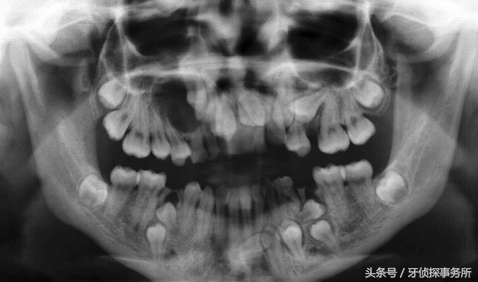

“懒”得咀嚼,牙齿在退化!爸妈深怕宝宝咬不动、嚼不碎不好消化,于是把宝宝的食物一律绞碎,精细的食物让宝宝的牙齿和口腔内外的肌肉得不到应有的锻炼,导致肌肉无力、萎缩,颌骨也不能很好地发育,但牙齿的数量并没有减少,所以儿童牙齿错合畸形的发病率也越来越高。

打碎了的食物往嘴里塞,就像“去了壳”的瓜子仁,少了嗑瓜子的兴趣和原味,会减少宝宝的兴趣哦。另外,精细的食物还容易诱发蛀牙,出现牙齿缺损、乳牙过早丢失、恒牙萌出间隙不足,进而造成牙齿排列不齐。所以一旦宝宝长了牙,能够自行咀嚼的时候,爸妈就该少些“操心”,好好的磨炼磨炼宝宝的小乳牙,以防长得横七竖八。